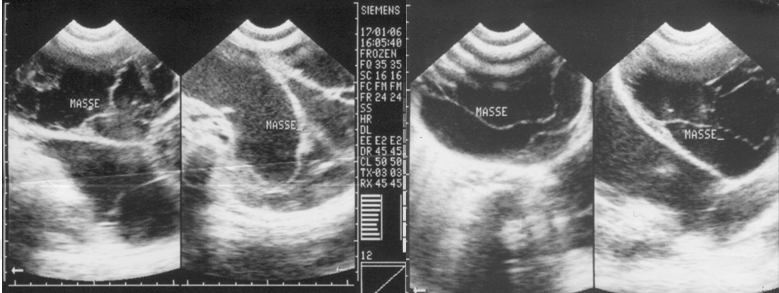

Abdominal ultrasound revealed the presence of a large cystic mass with multiple septa and mobile internal echoes (brown movements) from epigastrium to pelvis (Figure 3).

All the solid organs (liver, spleen, kidneys and pancreas) were normal but displaced by the mass. There was no ascites. Diagnosis of "mesothelium tumoral mass" or "peritoneal myxoma" was evoked.

Figure 3: Abdominal Ultrasound dysplaied the presence of a large cystic mass with multiple septa and liquid with brown movements inside.